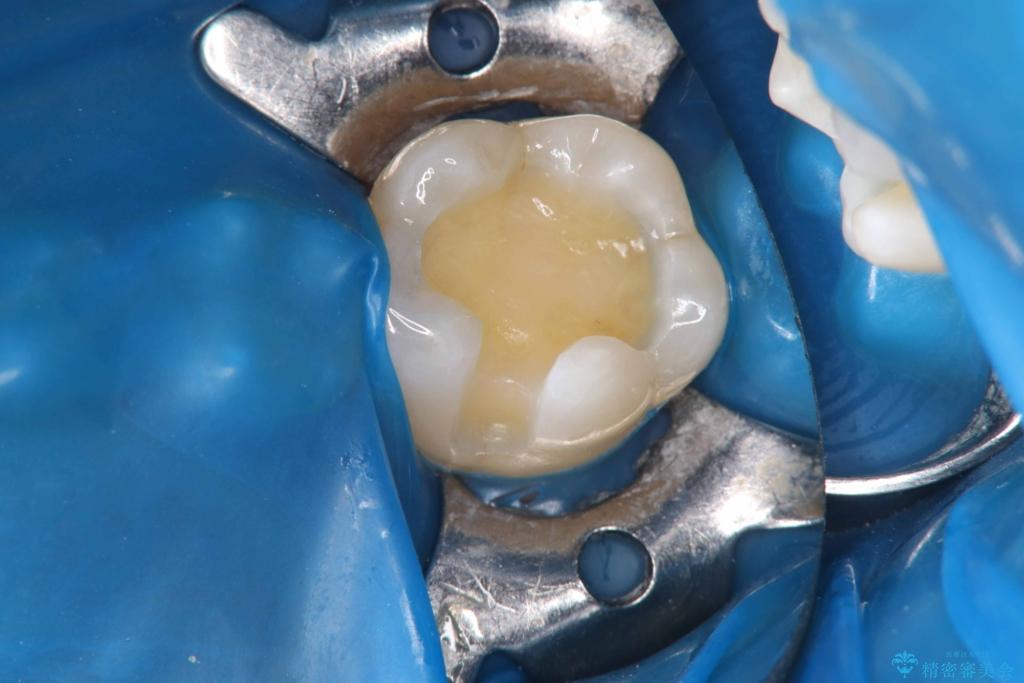

セラミックインレー装着時には、唾液が入らないようラバーダムシートを使用し、接着精度を高めることで、長く安心して使っていただける治療を心がけています。